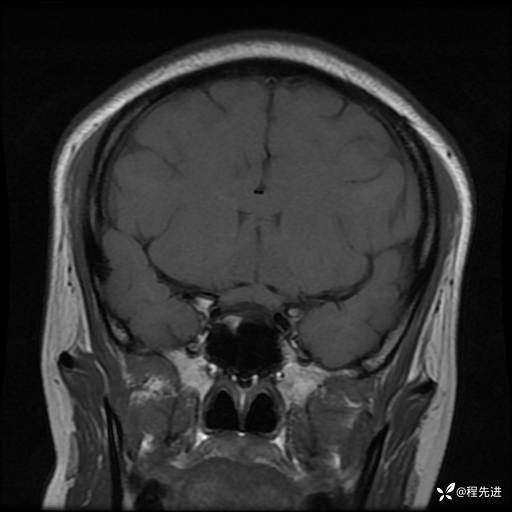

MRI平扫+增强:

T1: